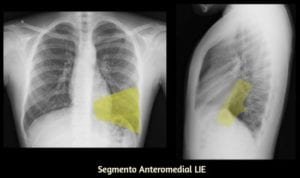

Início/Você Descreve Corretamente a Localização das Imagens Pulmonares nos Exames Radiológicos?/raiox do pulmao 21 raiox do pulmao 21